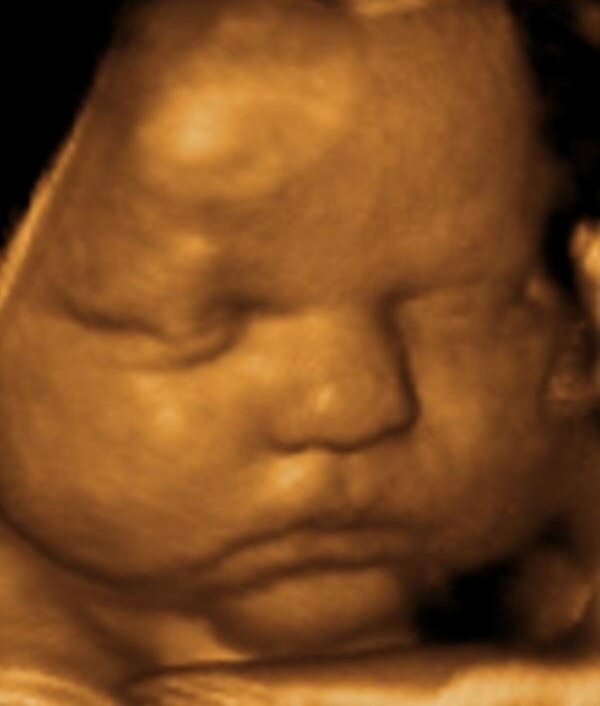

ΠΠ°Π½Π½ΡΠΉ Π²ΠΈΠ΄ ΠΎΠ±ΡΠ»Π΅Π΄ΠΎΠ²Π°Π½ΠΈΡ Π²ΡΠ°ΡΠΈ ΡΠ°ΠΊΠΆΠ΅ Π½Π°Π·ΡΠ²Π°ΡΡ Β«ΠΆΠΈΠ²ΡΠΌΒ» Π£ΠΠ. ΠΡΠΎΡ Π½ΠΎΠ²Π΅ΠΉΡΠΈΠΉ ΠΌΠ΅ΡΠΎΠ΄ ΠΏΠΎΠ·Π²ΠΎΠ»ΡΠ΅Ρ ΡΠΏΠ΅ΡΠΈΠ°Π»ΠΈΡΡΠ°ΠΌ, ΠΊΠΎΡΠΎΡΡΠ΅ Π΅Π³ΠΎ ΠΏΡΠΎΠ²ΠΎΠ΄ΡΡ, Π²ΠΈΠ΄Π΅ΡΡ Π½Π΅ ΡΡΠ°ΡΠΈΡΠ½ΡΡ ΠΊΠ°ΡΡΠΈΠ½ΠΊΡ Π½Π° ΠΌΠΎΠ½ΠΈΡΠΎΡΠ΅ ΡΠ»ΡΡΡΠ°Π·Π²ΡΠΊΠΎΠ²ΠΎΠ³ΠΎ Π°ΠΏΠΏΠ°ΡΠ°ΡΠ°, Π° ΠΏΠΎΠ»Π½ΠΎΡΠ΅Π½Π½ΠΎΠ΅ ΠΎΠ±ΡΠ΅ΠΌΠ½ΠΎΠ΅ ΠΈΠ·ΠΎΠ±ΡΠ°ΠΆΠ΅Π½ΠΈΠ΅.

ΠΠ°Π½Π½ΡΠΉ Π²ΠΈΠ΄ ΠΎΠ±ΡΠ»Π΅Π΄ΠΎΠ²Π°Π½ΠΈΡ Ρ ΠΊΠ°ΠΆΠ΄ΡΠΌ Π΄Π½Π΅ΠΌ ΡΡΠ°Π½ΠΎΠ²ΠΈΡΡΡ Π²ΡΠ΅ Π±ΠΎΠ»Π΅Π΅ ΠΏΠΎΠΏΡΠ»ΡΡΠ½ΡΠΌ ΡΡΠ΅Π΄ΠΈ Π±ΡΠ΄ΡΡΠΈΡ ΡΠΎΠ΄ΠΈΡΠ΅Π»Π΅ΠΉ. ΠΡΠΈΡ ΠΎΠ΄Ρ Π½Π° ΠΏΡΠΎΠ²Π΅Π΄Π΅Π½ΠΈΠ΅ 4D Π£ΠΠ, ΠΏΠ°ΠΏΡ ΠΈ ΠΌΠ°ΠΌΡ Π²ΠΈΠ΄ΡΡ ΡΠ²ΠΎΠ΅Π³ΠΎ ΠΌΠ°Π»ΡΡΠ° Π½Π° ΠΌΠΎΠ½ΠΈΡΠΎΡΠ΅, ΠΊΠΎΡΠΎΡΡΠΉ ΠΎΠ±ΡΡΠ½ΠΎ Π΄Π²ΠΈΠΆΠ΅ΡΡΡ ΠΈΠ»ΠΈ ΡΠΎΠ²Π΅ΡΡΠ°Π΅Ρ ΠΊΠ°ΠΊΠΈΠ΅-Π»ΠΈΠ±ΠΎ Π΄Π²ΠΈΠΆΠ΅Π½ΠΈΡ ΡΡΡΠΊΠ°ΠΌΠΈ ΠΈΠ»ΠΈ Π½ΠΎΠΆΠΊΠ°ΠΌΠΈ. Π’Π°ΠΊΠΎΠ΅ ΠΈΡΡΠ»Π΅Π΄ΠΎΠ²Π°Π½ΠΈΠ΅ ΠΏΡΠΈΠ²ΠΎΠ΄ΠΈΡ Π±ΡΠ΄ΡΡΠΈΡ ΡΠΎΠ΄ΠΈΡΠ΅Π»Π΅ΠΉ Π² Π½Π°ΡΡΠΎΡΡΠΈΠΉ Π²ΠΎΡΡΠΎΡΠ³.

ΠΠ·ΠΎΠ±ΡΠ°ΠΆΠ΅Π½ΠΈΠ΅, ΠΊΠΎΡΠΎΡΠΎΠ΅ ΡΠΎΡΠΌΠΈΡΡΠ΅ΡΡΡ Π²ΡΠ»Π΅Π΄ΡΡΠ²ΠΈΠ΅ ΠΎΡΡΠ°ΠΆΠ΅Π½ΠΈΡ Π·Π²ΡΠΊΠΎΠ²ΡΡ Π²ΠΎΠ»Π½ ΠΎΠΏΡΠ΅Π΄Π΅Π»Π΅Π½Π½ΠΎΠΉ ΡΠ°ΡΡΠΎΡΡ ΠΏΠΎΡΠ²Π»ΡΠ΅ΡΡΡ Π½Π° ΡΠΏΠ΅ΡΠΈΠ°Π»ΡΠ½ΠΎΠΌ ΠΌΠΎΠ½ΠΈΡΠΎΡΠ΅. ΠΠΎ Π²ΡΠ΅ΠΌΡ ΠΈΡΡΠ»Π΅Π΄ΠΎΠ²Π°Π½ΠΈΡ Π΅Π³ΠΎ Π²ΠΈΠ΄ΠΈΡ ΠΊΠ°ΠΊ Π΄ΠΎΠΊΡΠΎΡ, ΡΠ°ΠΊ ΠΈ Π±ΡΠ΄ΡΡΠ°Ρ ΠΌΠ°ΠΌΠ°. Π ΡΡΠ΅ΡΡΠ΅ΠΌ ΡΡΠΈΠΌΠ΅ΡΡΡΠ΅ Π±Π΅ΡΠ΅ΠΌΠ΅Π½Π½ΠΎΡΡΠΈ Π²ΠΈΠ΄Π½Ρ Π½Π΅ ΡΠΎΠ»ΡΠΊΠΎ Π°ΠΊΡΠΈΠ²Π½ΡΠ΅ Π΄Π²ΠΈΠΆΠ΅Π½ΠΈΡ ΠΌΠ°Π»ΡΡΠ°, ΠΊΠΎΠ³Π΄Π° ΠΎΠ½ ΡΠΎΡΠ΅Ρ ΠΏΠ°Π»ΡΡΠΈΠΊ ΠΈΠ»ΠΈ ΠΊΡΡΡΠΈΡ Π½ΠΎΠΆΠΊΠΎΠΉ, Π½ΠΎ ΡΠ°ΠΊΠΆΠ΅ ΠΈ Π΅Π³ΠΎ ΠΌΠΈΠΌΠΈΠΊΠ°.

ΠΠΎ Π²ΡΠ΅ΠΌΡ Π½Π°Π²Π΅Π΄Π΅Π½ΠΈΡ Π½Π° Π½Π΅Π³ΠΎ ΡΠ»ΡΡΡΠ°Π·Π²ΡΠΊΠΎΠ²ΠΎΠ³ΠΎ Π΄Π°ΡΡΠΈΠΊΠ° ΡΠ΅Π±Π΅Π½ΠΎΠΊ ΠΎΠ±ΡΡΠ½ΠΎ Π½Π°Ρ ΠΌΡΡΠΈΠ²Π°Π΅Ρ Π»ΠΎΠ±ΠΈΠΊ ΠΈΠ»ΠΈ ΡΠ»ΡΠ±Π°Π΅ΡΡΡ.

ΠΠΎΡΠ²Π»Π΅Π½ΠΈΠ΅ Ρ ΠΌΠ°Π»ΡΡΠ° ΡΠ°Π·Π»ΠΈΡΠ½ΡΡ ΡΠΌΠΎΡΠΈΠΉ ΡΡΠ°Π·Ρ ΠΆΠ΅ ΠΏΠΎΠ΄Π΄Π°Π΅ΡΡΡ ΡΡΠ°ΠΊΡΠΎΠ²ΠΊΠ΅. Π’Π°ΠΊ, Π±ΡΠ΄ΡΡΠ°Ρ ΠΌΠ°ΠΌΠΎΡΠΊΠ° ΡΡΠΈΡΠ°Π΅Ρ, ΡΡΠΎ Π΅ΡΠ»ΠΈ ΠΌΠ°Π»ΡΡ Ρ ΠΌΡΡΠΈΡΡΡ, ΡΠΎ Π΅ΠΌΡ ΠΏΠ»ΠΎΡ ΠΎ. ΠΡΠΎ ΡΠΎΠ²ΡΠ΅ΠΌ Π½Π΅ ΡΠ°ΠΊ. ΠΡΠΎΡΠ²Π»Π΅Π½ΠΈΠ΅ ΡΠΌΠΎΡΠΈΠΉ Π²ΠΎ Π²Π½ΡΡΡΠΈΡΡΡΠΎΠ±Π½ΠΎΠΌ ΠΏΠ΅ΡΠΈΠΎΠ΄Π΅ ΡΠ°Π·Π²ΠΈΡΠΈΡ β Π²ΡΠ΅Π³ΠΎ Π»ΠΈΡΡ ΠΏΠΎΠ²Π΅Π΄Π΅Π½ΡΠ΅ΡΠΊΠΈΠΉ ΡΠ°ΠΊΡΠΎΡ

. ΠΠ΅ΡΠ΅ΠΌΠ΅Π½Π½ΠΎΠΉ ΠΆΠ΅Π½ΡΠΈΠ½Π΅ Π½Π΅ ΡΡΠΎΠΈΡ ΠΏΠ°Π½ΠΈΠΊΠΎΠ²Π°ΡΡ, Π΅ΡΠ»ΠΈ ΠΎΠ½Π° ΡΠ²ΠΈΠ΄Π΅Π»Π° Π½Π° Π»ΠΈΡΠ΅ ΡΠ²ΠΎΠ΅Π³ΠΎ Π±ΡΠ΄ΡΡΠ΅Π³ΠΎ ΡΠ΅Π±Π΅Π½ΠΊΠ° ΠΊΠ°ΠΊΡΡ-ΡΠΎ Π³ΡΠΈΠΌΠ°ΡΡ Π½Π΅ΡΠ΄ΠΎΠ²ΠΎΠ»ΡΡΡΠ²ΠΈΡ ΠΈΠ»ΠΈ Π±ΠΎΠ»ΠΈ. ΠΠ°ΡΡΠΎΡΡΠΈΠΉ ΡΠΌΠΎΡΠΈΠΎΠ½Π°Π»ΡΠ½ΡΠΉ ΡΠΎΠ½ ΡΡΠΎΡΠΌΠΈΡΡΠ΅ΡΡΡ Ρ ΠΌΠ°Π»ΡΡΠ° ΡΠΆΠ΅ ΠΏΠΎΡΠ»Π΅ Π΅Π³ΠΎ ΡΠΎΠΆΠ΄Π΅Π½ΠΈΡ.Π‘ΡΡΠ΅ΡΡΠ²Π΅Π½Π½ΡΠΉ ΠΏΠ»ΡΡ Π΄Π°Π½Π½ΠΎΠΉ ΠΏΡΠΎΡΠ΅Π΄ΡΡΡ β Π²ΠΎΠ·ΠΌΠΎΠΆΠ½ΠΎΡΡΡ Π·Π°ΠΏΠΈΡΠΈ ΠΈΠ·ΠΎΠ±ΡΠ°ΠΆΠ΅Π½ΠΈΡ Π½Π° ΡΠ°Π·Π»ΠΈΡΠ½ΡΠ΅ ΡΠ»Π΅ΠΊΡΡΠΎΠ½Π½ΡΠ΅ Π½ΠΎΡΠΈΡΠ΅Π»ΠΈ. ΠΡΠ΄ΡΡΠΈΠ΅ ΡΠΎΠ΄ΠΈΡΠ΅Π»ΠΈ ΠΌΠΎΠ³ΡΡ ΠΏΠΎΠ»ΡΡΠΈΡΡ Π²ΠΈΠ΄Π΅ΠΎ ΠΈΠ»ΠΈ ΡΠΎΡΠΎ ΡΠ²ΠΎΠ΅Π³ΠΎ ΠΌΠ°Π»ΡΡΠ° Π½Π° ΡΠΏΠ΅ΡΠΈΠ°Π»ΡΠ½ΡΠΉ Π΄ΠΈΡΠΊ. Π’Π°ΠΊΠΆΠ΅ ΡΠ½ΠΈΠΌΠΎΠΊ ΠΌΠΎΠΆΠ½ΠΎ ΡΠ°ΡΠΏΠ΅ΡΠ°ΡΠ°ΡΡ Π½Π΅ΠΏΠΎΡΡΠ΅Π΄ΡΡΠ²Π΅Π½Π½ΠΎ Π² ΠΊΠ°Π±ΠΈΠ½Π΅ΡΠ΅ Π£ΠΠ. ΠΠ±ΡΡΠ½ΠΎ ΡΠ°ΠΊΠ°Ρ ΠΏΠ΅ΡΠ²Π°Ρ ΡΠΎΡΠΎΠ³ΡΠ°ΡΠΈΡ ΠΌΠ°Π»ΡΡΠ° Π²ΡΠ·ΡΠ²Π°Π΅Ρ Ρ Π±ΡΠ΄ΡΡΠΈΡ ΡΠΎΠ΄ΠΈΡΠ΅Π»Π΅ΠΉ ΡΠ»Π΅Π·Ρ ΡΠ°Π΄ΠΎΡΡΠΈ ΠΈ Π½Π΅ΠΏΠΎΠ΄Π΄Π΅Π»ΡΠ½ΡΠΉ Π²ΠΎΡΡΠΎΡΠ³.